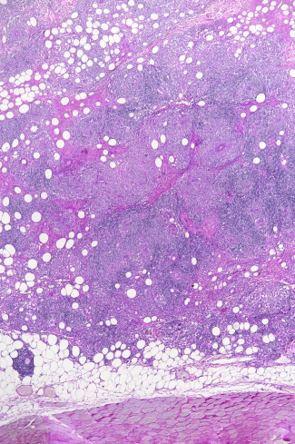

Mikroskopische Aufnahme des Gewebes - geringe Vergrösserung. Mikroskopische Aufnahme des Gewebes - starke Vergrösserung. Bei Aufnahme: Dr. U. Hetzel den dunklen Punkten handelt es sich um Entzündungszellen. Aufnahme: Dr. U. Hetzel

Das Krankheitsbild von Balu ist sehr unüblich. Nicht zuletzt muss selbst bei einem so jungen Hund auch an Hautkrebs gedacht werden, weshalb wir uns zur Entnahme von Gewebeproben unter einer kurzen Narkose entscheiden. Der Gewebebefund ist ebenfalls unüblich: Der Pathologe diagnostiziert einen bestimmten Typ einer entzündlichen Veränderung der Haut (Dermatitis). Eine erweiterte Gewebeuntersuchung weist nach, dass der Hund nicht an einer Leishmaniose leidet - diese parasitäre Krankheit könnte nämlich ein ähnliches Bild verursachen. Abschliessend wird also die Diagnose einer "pyogranulomatösen Dermatitis/Adnexitis" gestellt.